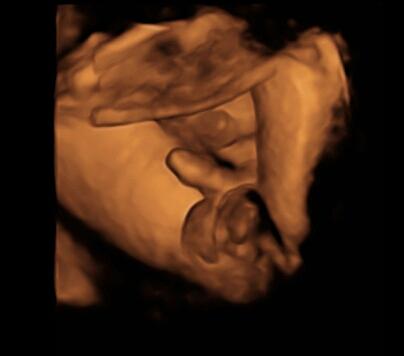

Hallo ich bin neu hier, letzte Woche waren wir beim Ultraschall und die Ärztin meinte, dass es wahrscheinlich ein Junge wird. Was meint ihr, ist die Aussage wirklich schon zu 100% sicher? Liebe Grüße

Bild zu 19. SSW Junge oder Mädchen? - Schwanger - wer noch? Rund um die Schwangerschaft

hät jetzt auch junge gesagt,aber ich habe lieber bis zur 23 ssw gewartet da man es bei der Fd in 3D wirklich gesehen hat und ich somit gleich ein "Beweisbild" mit nach hause bekommen habe lg stromin 41 ssw

ich sehe eher Mädchen !!!!! Das was offensichtlich ist,ist die Nabelschnur ....ich sehe Stückchen weiter links etwas anderes!!!! Alles ohne Gewähr!!!!

ich bin ja kein arzt und stimme meinen vorrednern zu, 100%ig ist es erst später bei 3d ultraschall oder geburt ... aber ICH als nicht-arzt sehe da definitiv einen schiedel und die zugehörigen bällchen ... ich gaube, in der 19. ssw hat sich der "zipfel" bei den mädchen schon zurück gebildet ...

Sieht ganz klar nach junge aus. Sah bei mir haargenau so aus. Mein Sohn ist nun 8 Monate alt.

Hallo, das ist ziemlich eindeutig. Sah bei meinen Jungs ganz ähnlich aus! LG, Julia